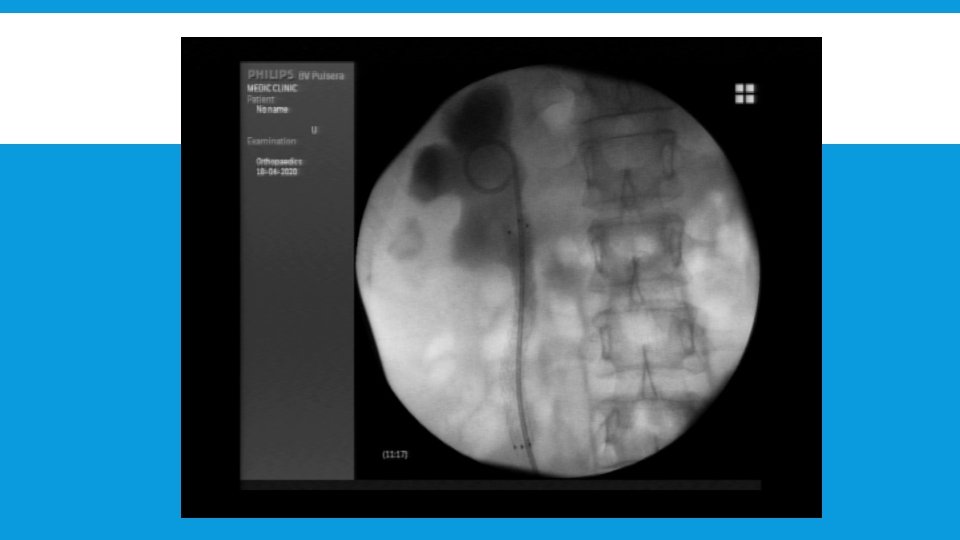

CASE REPORT: TRONG THỦ THUẬT Quan sát trực tiếp dưới C-arm

TRONG THỦ THUẬT